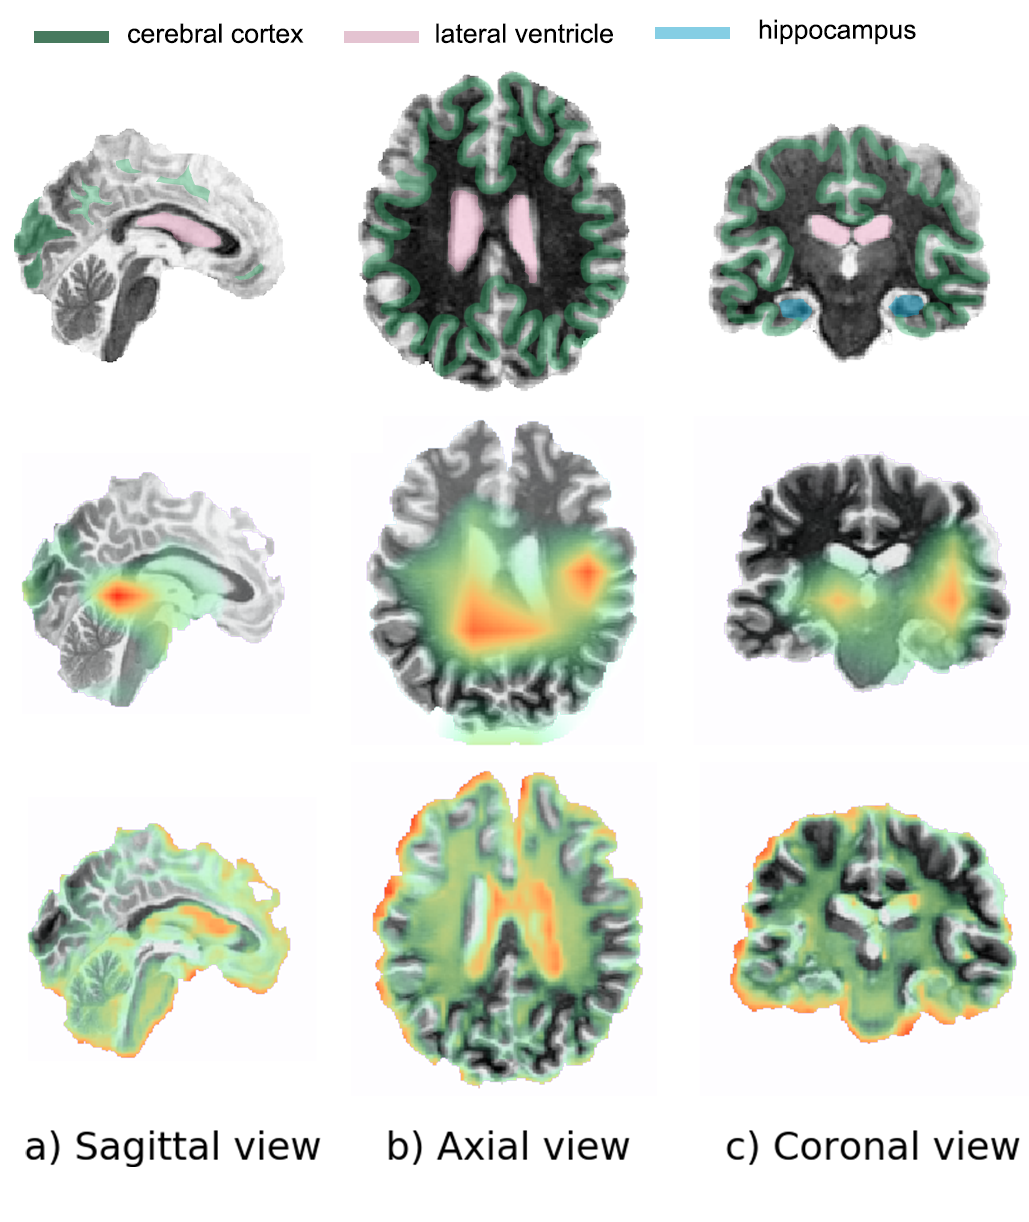

The attention heatmap of the Grad-CAM on 3D-ResAttNet34 result is presented in Fig. 6. For comparison, the hippocampus, lateral ventricle and cerebral cortex areas on the input sMRI image in the first row are labeled to show the important areas for Alzheimer’s disease diagnosis. In the second row, we have applied the activation mapping heat-map to the last convolutional layer (i.e the fourth layer in this case). The heatmap is blurry because the last convolutional layer of 3D-ResAttNet34 is only of size 6×7×66766\times 7\times 6. The heat map tends to show global information. To obtain a higher resolution and more detailed 3D class activation mapping heat-map, we have applied the 3D Grad-CAM to the lower convolutional layer (the third layer), as shown in the third row of Fig. 6. It is of size 46×55×4646554646\times 55\times 46 heat-map and thus provides more detail information. It identifies and highlights the hippocampus, lateral ventricle and most parts of the cortex as important areas, which matches the human expert’s approach [24, 62]. However, as mentioned in [63], the lower layer in deep CNN models responds more to corners and edge/color conjunctions. Therefore, edges are highlighted as well.

Figure 6: Sagittal, Axial and coronal view of the brain MRI and the visual explanation heatmaps. The first row shows the highlighted cerebral cortex, lateral ventricle, and hippocampus areas in sMRI images. The second row shows the visualization by applying the Grad-Cam to the fourth convolutional layer. The third row shows the visualization by applying the Grad-Cam to the third layer.